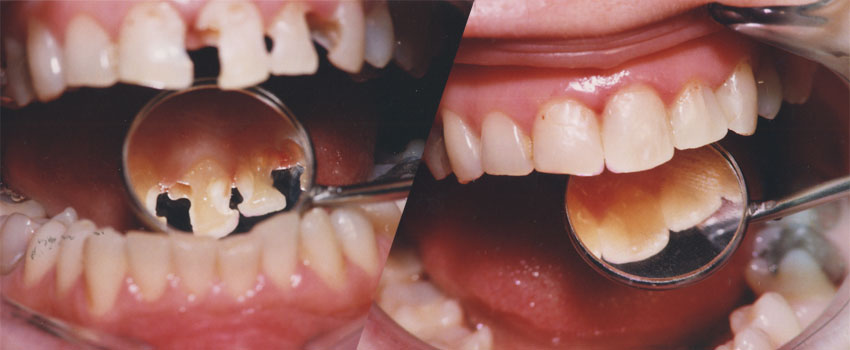

Upotreba savremenih nanohibridnih kompozita renomiranih svetskih proizvođača omugućuje izradu plombi vrhuskog kvaltiteta i estetike.

Rekonstrukcijom zuba po boji, obliku i veličini plombe izgledaju potpuno prirodno i traju dugi niz godina.